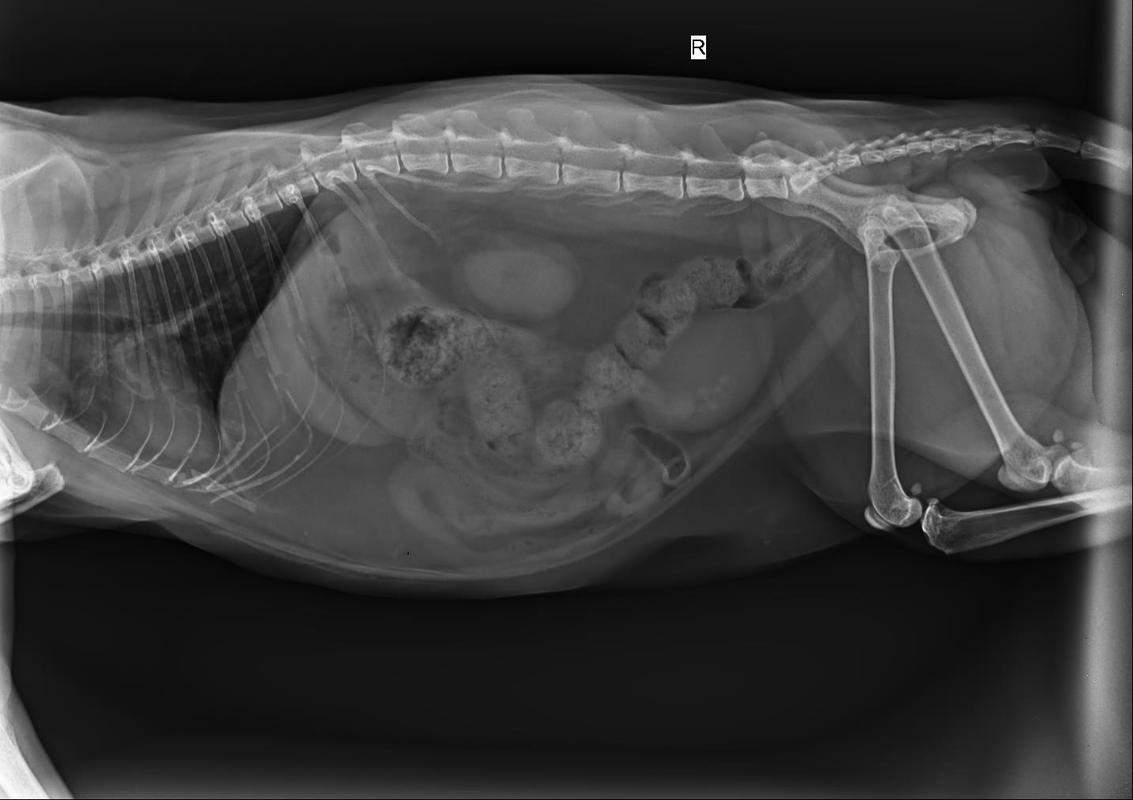

猫咪膀胱结石可能是由于应激反应或紧张情绪引起,导致不排尿,进而使尿液在尿道和膀胱中积累形成结石。 一旦诊断出猫咪患有膀胱结石,应立即开始治疗,因为这种情况可能对猫咪的生命构成威胁。 膀胱结石的确诊通常通过B超和X光检查。治疗方法可能包括导尿或手术,具体取决于结石的大小和类型。

〖贰〗、到宠物医院后需要先拍个X光片,来确定结石的大小,存在的位置。如果是小型结石可以用药物治疗,如果是大型的结石就需要手术治疗了。饲养者需要配合宠物医生的治疗工作,做好术前准备与术后调养工作,手术前需要饲养者安抚龙猫的情绪,然后准备手术。